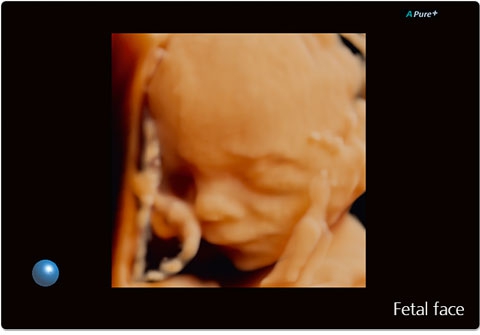

• ApliPure - технология повышения качества изображения

• Превосходное качество визуализации и детализации анатомических структур для широкого спектра областей использования.